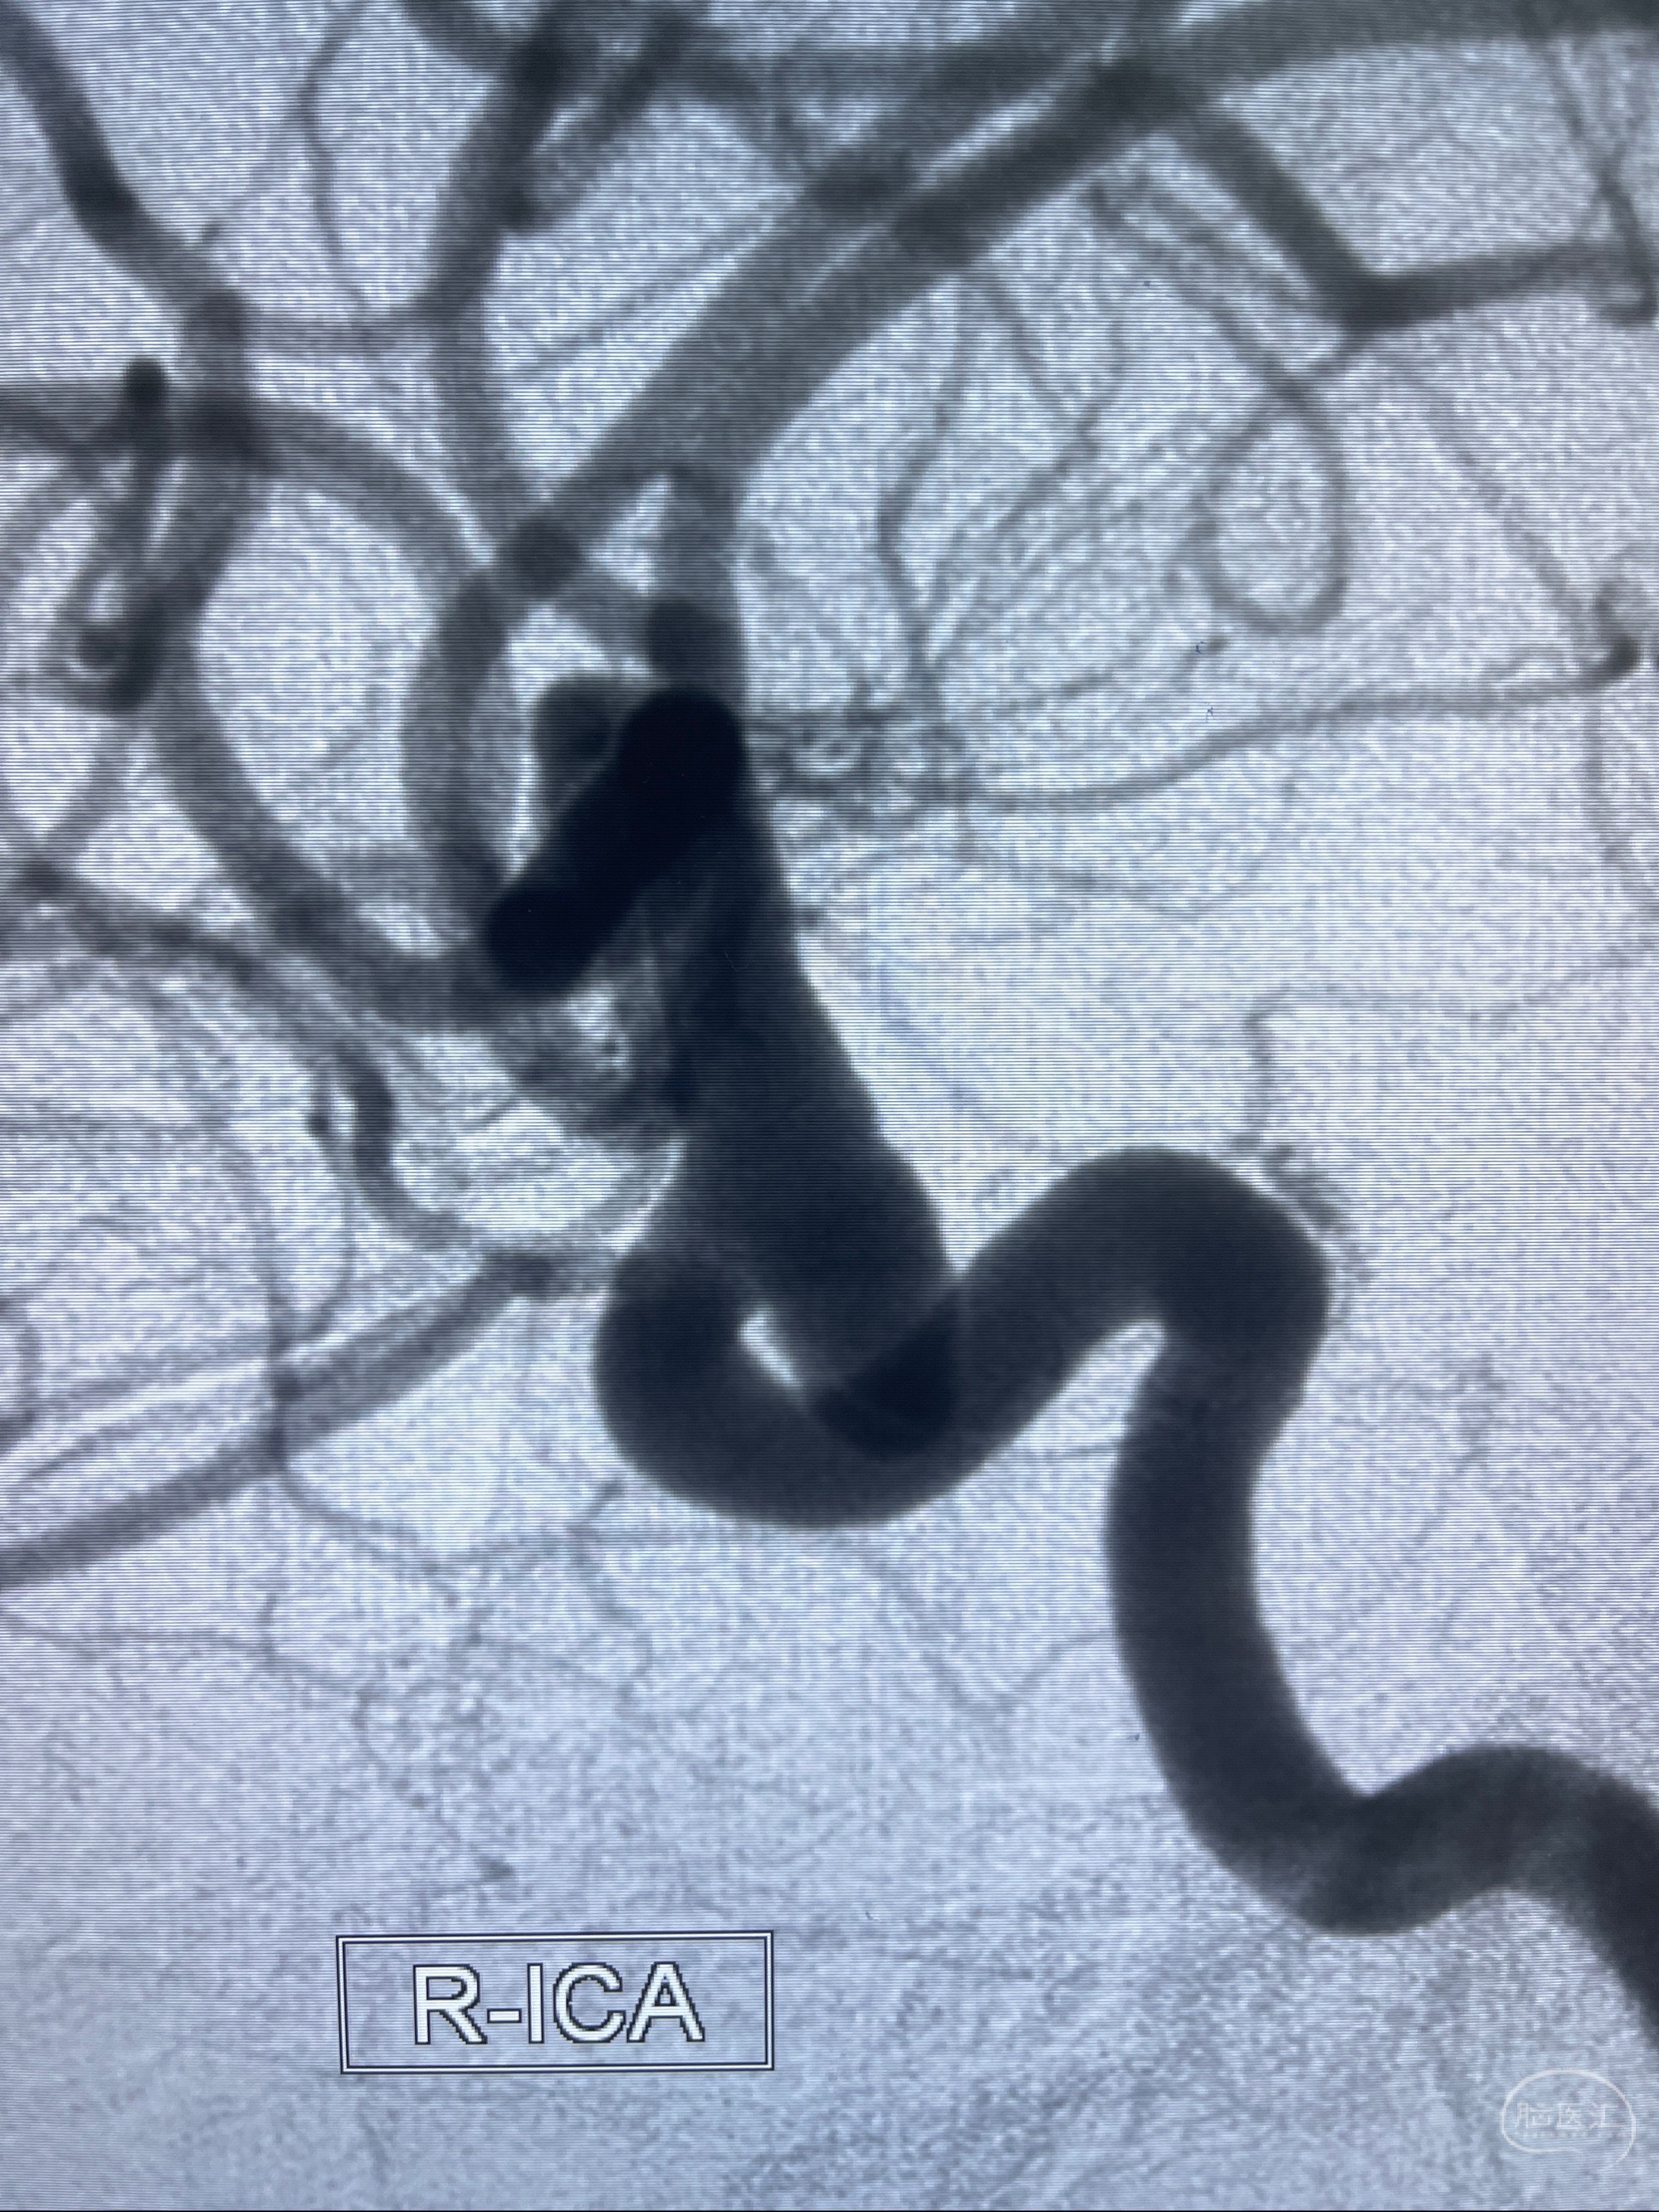

1.右侧颈内动脉眼动脉段动脉瘤

看原图,应该有两侧动脉瘤😅

2023-07-27全脑血管造影:双侧颈内动脉眼动脉段动脉瘤,右侧较大

2023-08-01全麻下行双侧颈眼动脉瘤支架辅助栓塞

- pipeling4.5-20mm

- pipeline 4.0-20mm